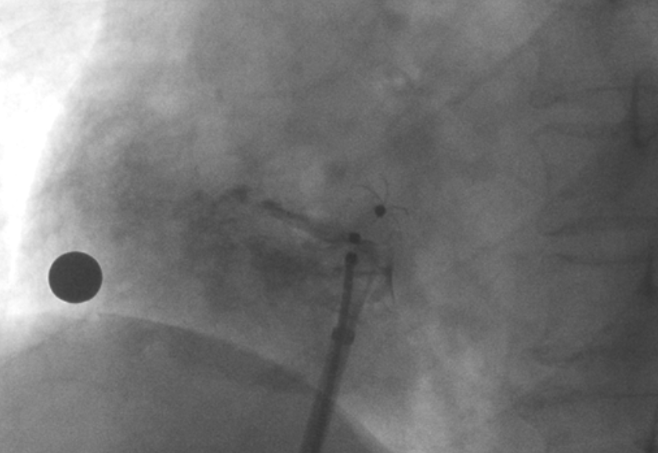

造影顯示PFO封堵完全,無殘余分流, 試驗(yàn)器械充分舒展并貼合良好

術(shù)中造影顯示患者為PFO且長隧道型,目前市場上已商業(yè)化的PFO封堵器難以滿足該患者解剖結(jié)構(gòu)封堵需求。迪創(chuàng)醫(yī)療自主研發(fā)的OmniSeal PFO封堵器自適應(yīng)性雙盤貼合設(shè)計能廣泛適應(yīng)不同PFO隧道長度的解剖結(jié)構(gòu)和形態(tài),其雙盤外包覆式阻流和隧道內(nèi)填充阻流相結(jié)合的雙重阻流設(shè)計,可為此患者實(shí)現(xiàn)有效封堵。與此同時,OmniSeal首創(chuàng)的完全可穿刺式設(shè)計,也為此患者最大程度地保留了房間隔區(qū)域穿刺通道,以實(shí)現(xiàn)全兼容未來可能的左心系統(tǒng)二次介入術(shù)。術(shù)終造影和心臟超聲顯示封堵完全、效果良好。作為OmniSeal的首例臨床應(yīng)用,本次手術(shù)的順利完成和優(yōu)異效果充分體現(xiàn)了產(chǎn)品的設(shè)計創(chuàng)新優(yōu)勢。